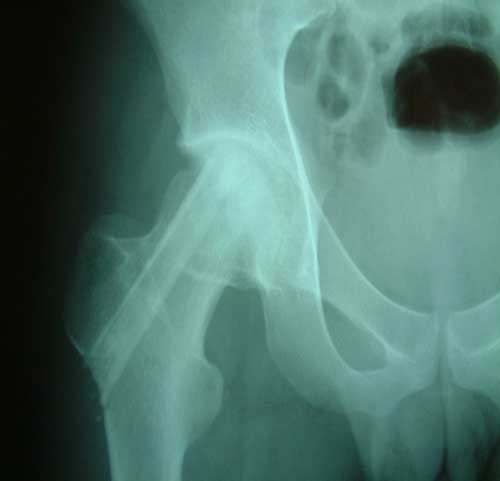

股骨头缺血性坏死MRI显示坏死区                  微创手术方法,采用隧道减压刮除死

BMP植入,异体骨支撑,恢复形态       手术后24个月X线片,关节塌陷未加重,关节功能良好,无疼痛